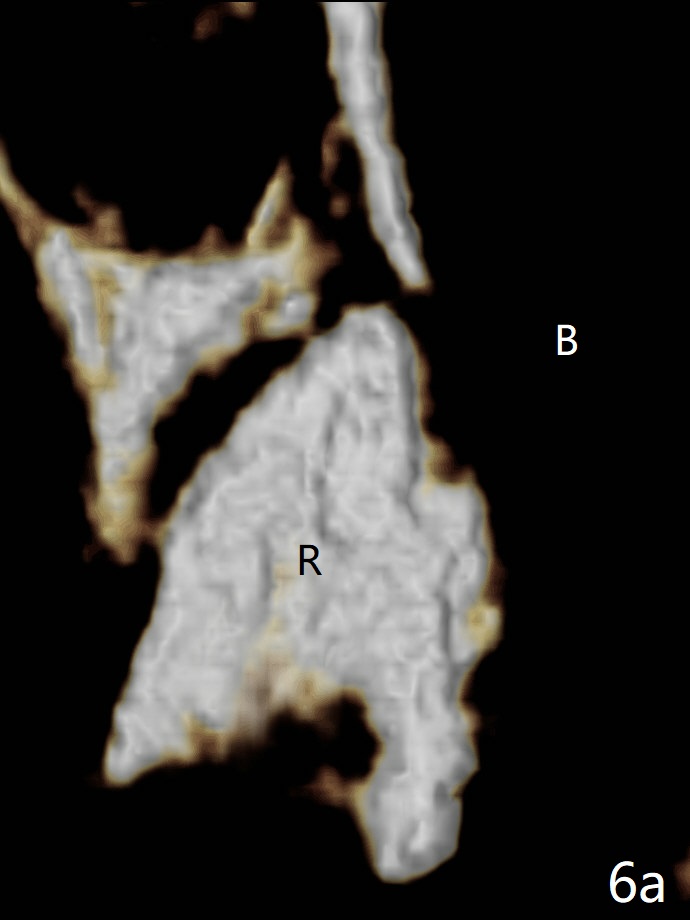

图六-a: 术前CT三维冠状切面显示左上5牙根(R);B: 颊侧。牙根拔除后(图六-b),根尖颊侧骨板缺失(<),